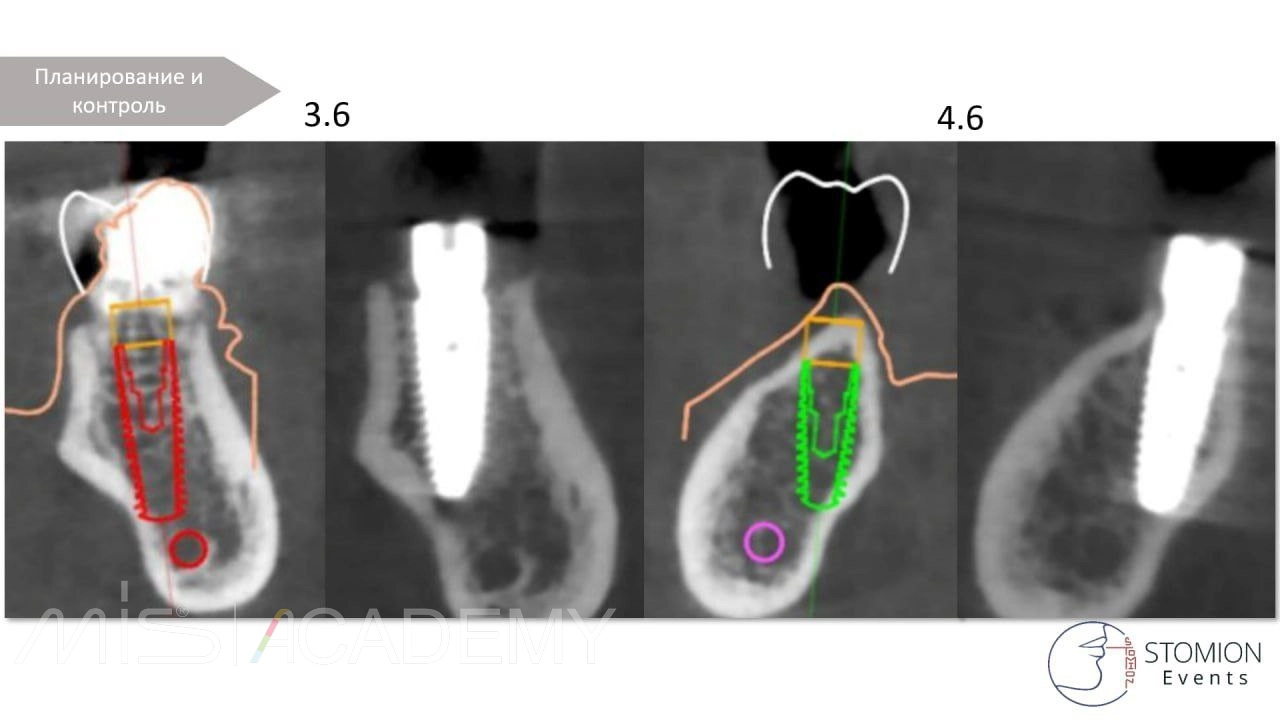

Диагноз: Адентия 4.6, мезиальный наклон 4.7, зубоальвеолярное выдвижение 1.6, перелом 3.6.

— 4.6 имплантация MIS C1 3,75х10 + connect 2мм + СТТ, фиксированный апикально к надкостнице, перекрыт расщепленным лоскутом.

— 3.7 удаление, одномоментная имплантация в перегородку, MIS C1 4,2×13 + connect 2мм, в лунки Bio-Oss S + A-PRF + немедленная нагрузка.

Контроль сразу после операции, далее 2-3-4 года.

Наблюдаем тенденцию образования кости вестибулярно в пришеечной зоне 4.6 — интересное наблюдение.